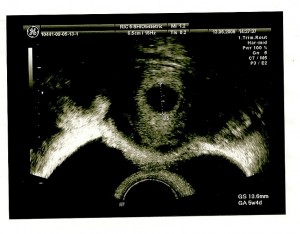

Convenceram-me a ir à urgência do hospital mais próximo para me ser feita uma ecografia. E assim foi! Lá fomos as três! Quando o médico começou a ecografia disse-me logo : “Está grávida, o saco está no útero e tem 5semanas e 4dias de gestação. Nota-se uma pequena perda de sangue por isso tenha cuidado, não faça muitos esforços. Parabéns!”.